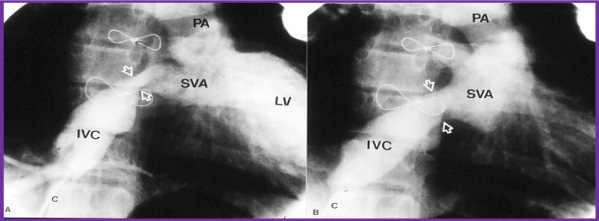

Baffle obstructions: Baffle obstruction develop in nearly10% of the patients [56]. Systemic venous obstruction is more frequently seen than pulmonary venous stenosis. The superior vena caval (SVC) obstruction is more often present than inferior vena caval stenosis [58]. Symptoms such as upper body edema indicative of SVC syndrome are rare and are usually detected by echo-Doppler studies, angiography or MRI performed either during routine follow-up or prior to considering placing pacemaker catheters. Balloon angioplasty of stenosed baffle obstruction (Figures 4 and 5) is often successful [58,59], however long-segment stenotic lesions would necessitate stent implantation (Figure 6) [36,37].

Figure 4. Selected cineangiographic frame from superior vena cava (SVC) injection in posterio-anterior view demonstrating stenosis (arrow) of the SVC baffle (A - PRE) in a patient who had Mustard procedure in the past. Following balloon angioplasty (B - POST), the narrowed segment improved (arrow). The azygos vein (Az) seen in A is no longer seen in B, presumably related relief of SVC obstruction following balloon angioplasty. C, catheter; LV left ventricle; PA, pulmonary artery. Reproduced from Rao PS, Wilson AD. (1992) Am Heart J 123: 244-248.

Figure 5. Selected cineangiographic frame from inferior vena cava (IVC) injection in right anterior oblique view demonstrating stenosis (arrows) of the IVC baffle (A - PRE) in a patient who had Mustard procedure several years previously. Following balloon angioplasty (B - POST), the narrowed segment improved (arrows). C, catheter; LV left ventricle; PA, pulmonary artery; SVA, systemic venous atrium. Reproduced from Rao PS, Wilson AD. (1992) Am Heart J 123: 244-248.